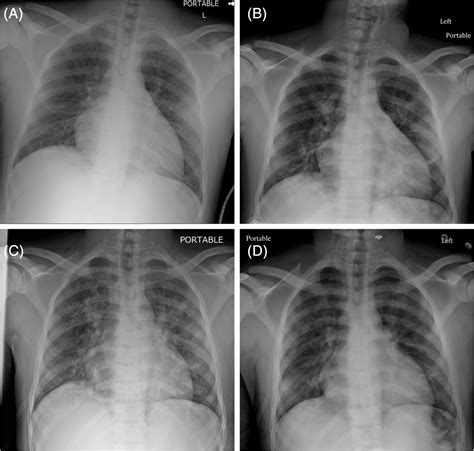

The Role of Diagnostic Imaging